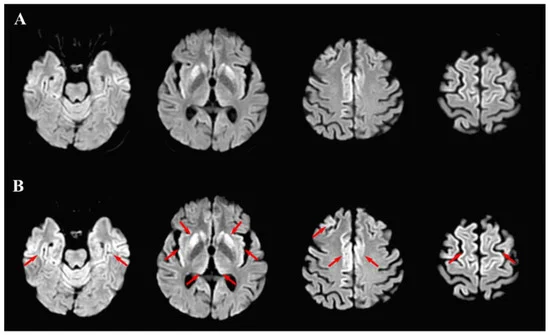

Acceleration of CJD after SC2 infection👇 Is the spike protein of the virus/vaxx accelerating existing neurodegeneration? If so, is the post-vaxx CJD really a new form of CJD or is it an enhancement of the disease by spike? #VaxxDependentEnhancement https://www.mdpi.com/2227-9059/9/11/1730/htm

Clinical and Radiological Deterioration in a Case of Creutzfeldt–Jakob Disease following SARS-CoV-2 Infection: Hints to Accelerated Age-Dependent Neurodegeneration Systemic inflammation and the host immune responses associated with certain viral infections may accelerate the rate of neurodegeneration in patients with Creutzfeldt–Jakob disease (CJD), a rare, transmissible neurodegenerative disease. However, the effects of the newly emerged SARS-CoV-2 infection on the pathogenesis of CJD are unknown. In this study, we describe the case of an elderly female patient with sporadic CJD that exhibited clinical deterioration with the emergence of seizures and radiological neurodegenerative progression following an infection with SARS-CoV-2 and severe COVID-19. Despite efforts to control the progression of the disease, a dismal outcome ensued. This report further evidences the age-dependent neurological effects of SARS-CoV-2 infection and proposes a vulnerability to CJD and increased CJD progression following COVID-19. mdpi.com

💡𝗖𝗮𝘀𝗲𝗥𝗲𝗽𝗼𝗿𝘁💡 "Clinical and Radiological Deterioration in a Case of Creutzfeldt–Jakob Disease following SARS-CoV-2 Infection: Hints to Accelerated Age-Dependent Neurodegeneration" 🔗https://www.mdpi.com/2227-9059/9/11/1730